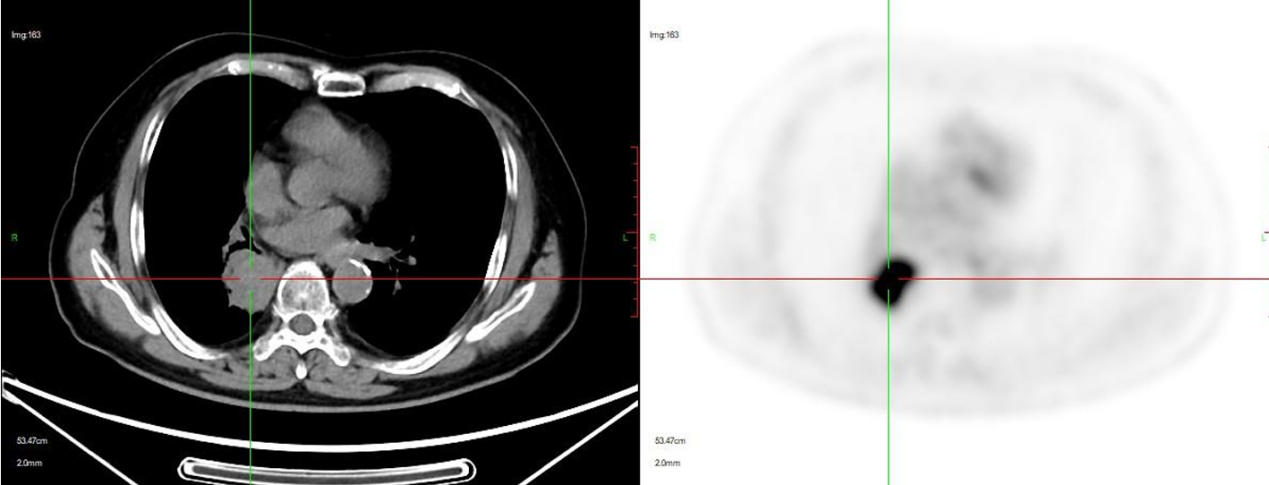

2024年7月3日于上海市肺科医院复查胸部CT示:右肺上、下叶肺癌伴阻塞性炎症,右肺门淋巴结肿大,较2024年3月4日CT局部略增大,双肺气肿,右肺下叶支扩伴感染。

2024年7月29日于外院行PET-CT示:右下肺门软组织肿块,考虑肺癌,伴肺不张及远端阻塞性肺炎,大小约32×23×34mm,SUVmax16.97,左肺上叶尖后段微小结节,FDG未见异常摄取。患者目前偶有刺激性咳嗽,为干咳,无胸闷、心慌、呼吸困难等不适。

辅助检查: 2024年7月3日,外院胸部CT:右肺上下叶肺癌伴阻塞性炎症,右肺门淋巴结肿大,较2024-03-04CT局部略增大,双肺其中,右肺下叶支扩伴感染。

2024年7月29日,外院PET-CT:右下肺门软组织肿块考虑肺癌伴肺不张及远端阻塞性肺炎,大小约32×23×34mm,SUVmax16.97,左肺上叶尖后段微小结节,FDG未见异常摄取。

放疗前:2024年7月29日,PET-CT:右肺癌治疗后:1、右下肺门处软组织肿块,FDG摄取增高,结合病史,考虑肺癌伴伴肺不张伴远端阻塞性炎症,病灶仍具有肿瘤活性。 2、左肺上叶尖后段微小结节,FDG未见异常摄取,建议CT定期随访。 3、双肺肺气肿;双肺散在慢性炎症。 4、肝脏囊肿。 5、所示椎体退行性变。